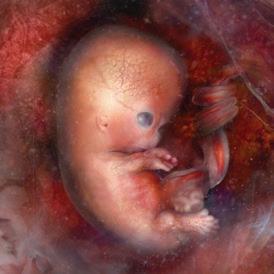

Day 1: Fertilization

The sperm joins with the egg to form one cell. This single cell contains the complex genetic makeup for every detail of a new human being. After fertilization, nothing new is added but oxygen, nutrition and time.1

1st Month: 1–4 Weeks

The first cell divides in two, and cell division continues as it travels down the fallopian tube to the uterus. Foundations of the brain, spinal cord, and nervous system are already established and by day 21 the heart begins to beat in a regular fashion.2 Muscles are forming, and arms, legs, eyes, and ears have begun to show.

2nd Month: 5–8 Weeks

By six weeks, brain waves can be detected.3 The jaw forms, including teeth and taste buds.4 The baby begins to swallow amniotic fluid, and sometimes hiccups.5 Fingers and toes are developing and at seven weeks the chest and abdomen are fully formed.6 Swimming in the amniotic fluid, she now looks like a miniature human infant.7,8

3rd Month: 9–12 Weeks

Unique fingerprints are evident and never change.9 The baby now sleeps, awakens, and exercises her muscles. The baby is very active. The gender can be visually determined and family resemblances may appear.10 At the end of the first trimester, all the organs and systems of her body are functioning.11

4th Month: 13–16 Weeks

By the end of the fourth month, the baby is 8–10 inches in length and weighs about one-half pound. Her ears are functioning and she hears her mother’s heartbeat, as well as external noises like music.12 Lifesaving surgery has been performed on babies at this age.

5th Month: 17–20 Weeks

If a sound is especially loud, the baby may jump in reaction to it. Thumb-sucking has been observed during the fifth month.13

6th Month: 21–24 Weeks

Oil and sweat glands are functioning. She grows rapidly in size and strength while her lungs become more developed.14

7th Month: 25–28 Weeks

The baby can now recognize her mother’s voice. She exercises by stretching and kicking. She uses the senses of hearing, touch and taste, and she can even look around with open eyes.15

8th Month: 29–32 Weeks

The baby swallows a gallon of amniotic fluid per day and often hiccups.16 The baby’s kicks are stronger and mom may be able to feel an elbow or heel against her abdomen.17

9th Month: 33–36 Weeks

Gaining one-half pound per week, the baby is getting ready for birth. The bones in her head are soft and flexible to more easily mold for the journey down the birth canal.18 Of the 45 generations of cell divisions before adulthood, 41 have already taken place. Only four more come before adolescence. Ninety percent of a person’s development happens in the womb.19